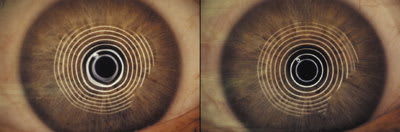

The patient was fit with the new reverse geometry soft lens design (Figure 3) to avoid the vaulting effect that occurs with traditional lenses on post-refractive surgery corneas. Figures 4 and 5 show the change in topography with the soft lens vs. without it.

| Figure 3. New reverse geometry SCLs OU. | Figure 4. Photokeratoscopy OD: without SCL (left) with SCL (right). |

Figure 5. Photokeratoscopy OS: without SCL (left) with SCL (right).  |